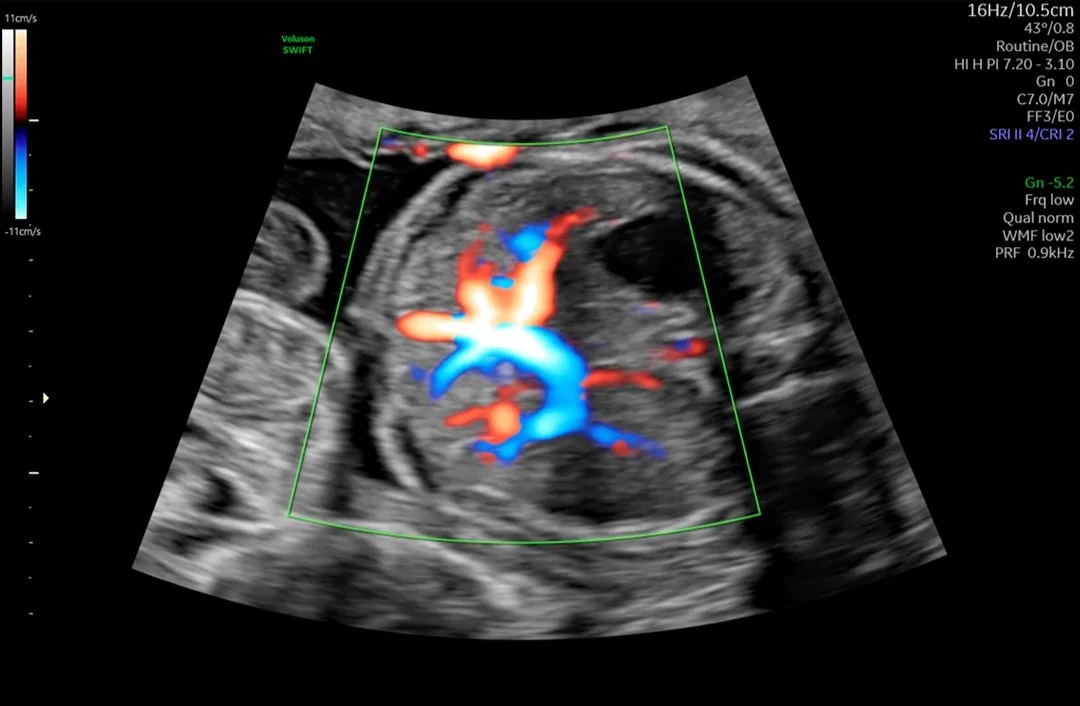

Obstetricia

Desde las primeras fases del embarazo hasta el nacimiento, la salud de la madre y el feto es su prioridad. Es por eso que nuestra prioridad es garantizar una adquisición de imágenes extraordinaria en todas las etapas del embarazo para explorar con confianza la anatomía del feto y detectar anomalías más rápida que nunca antes.